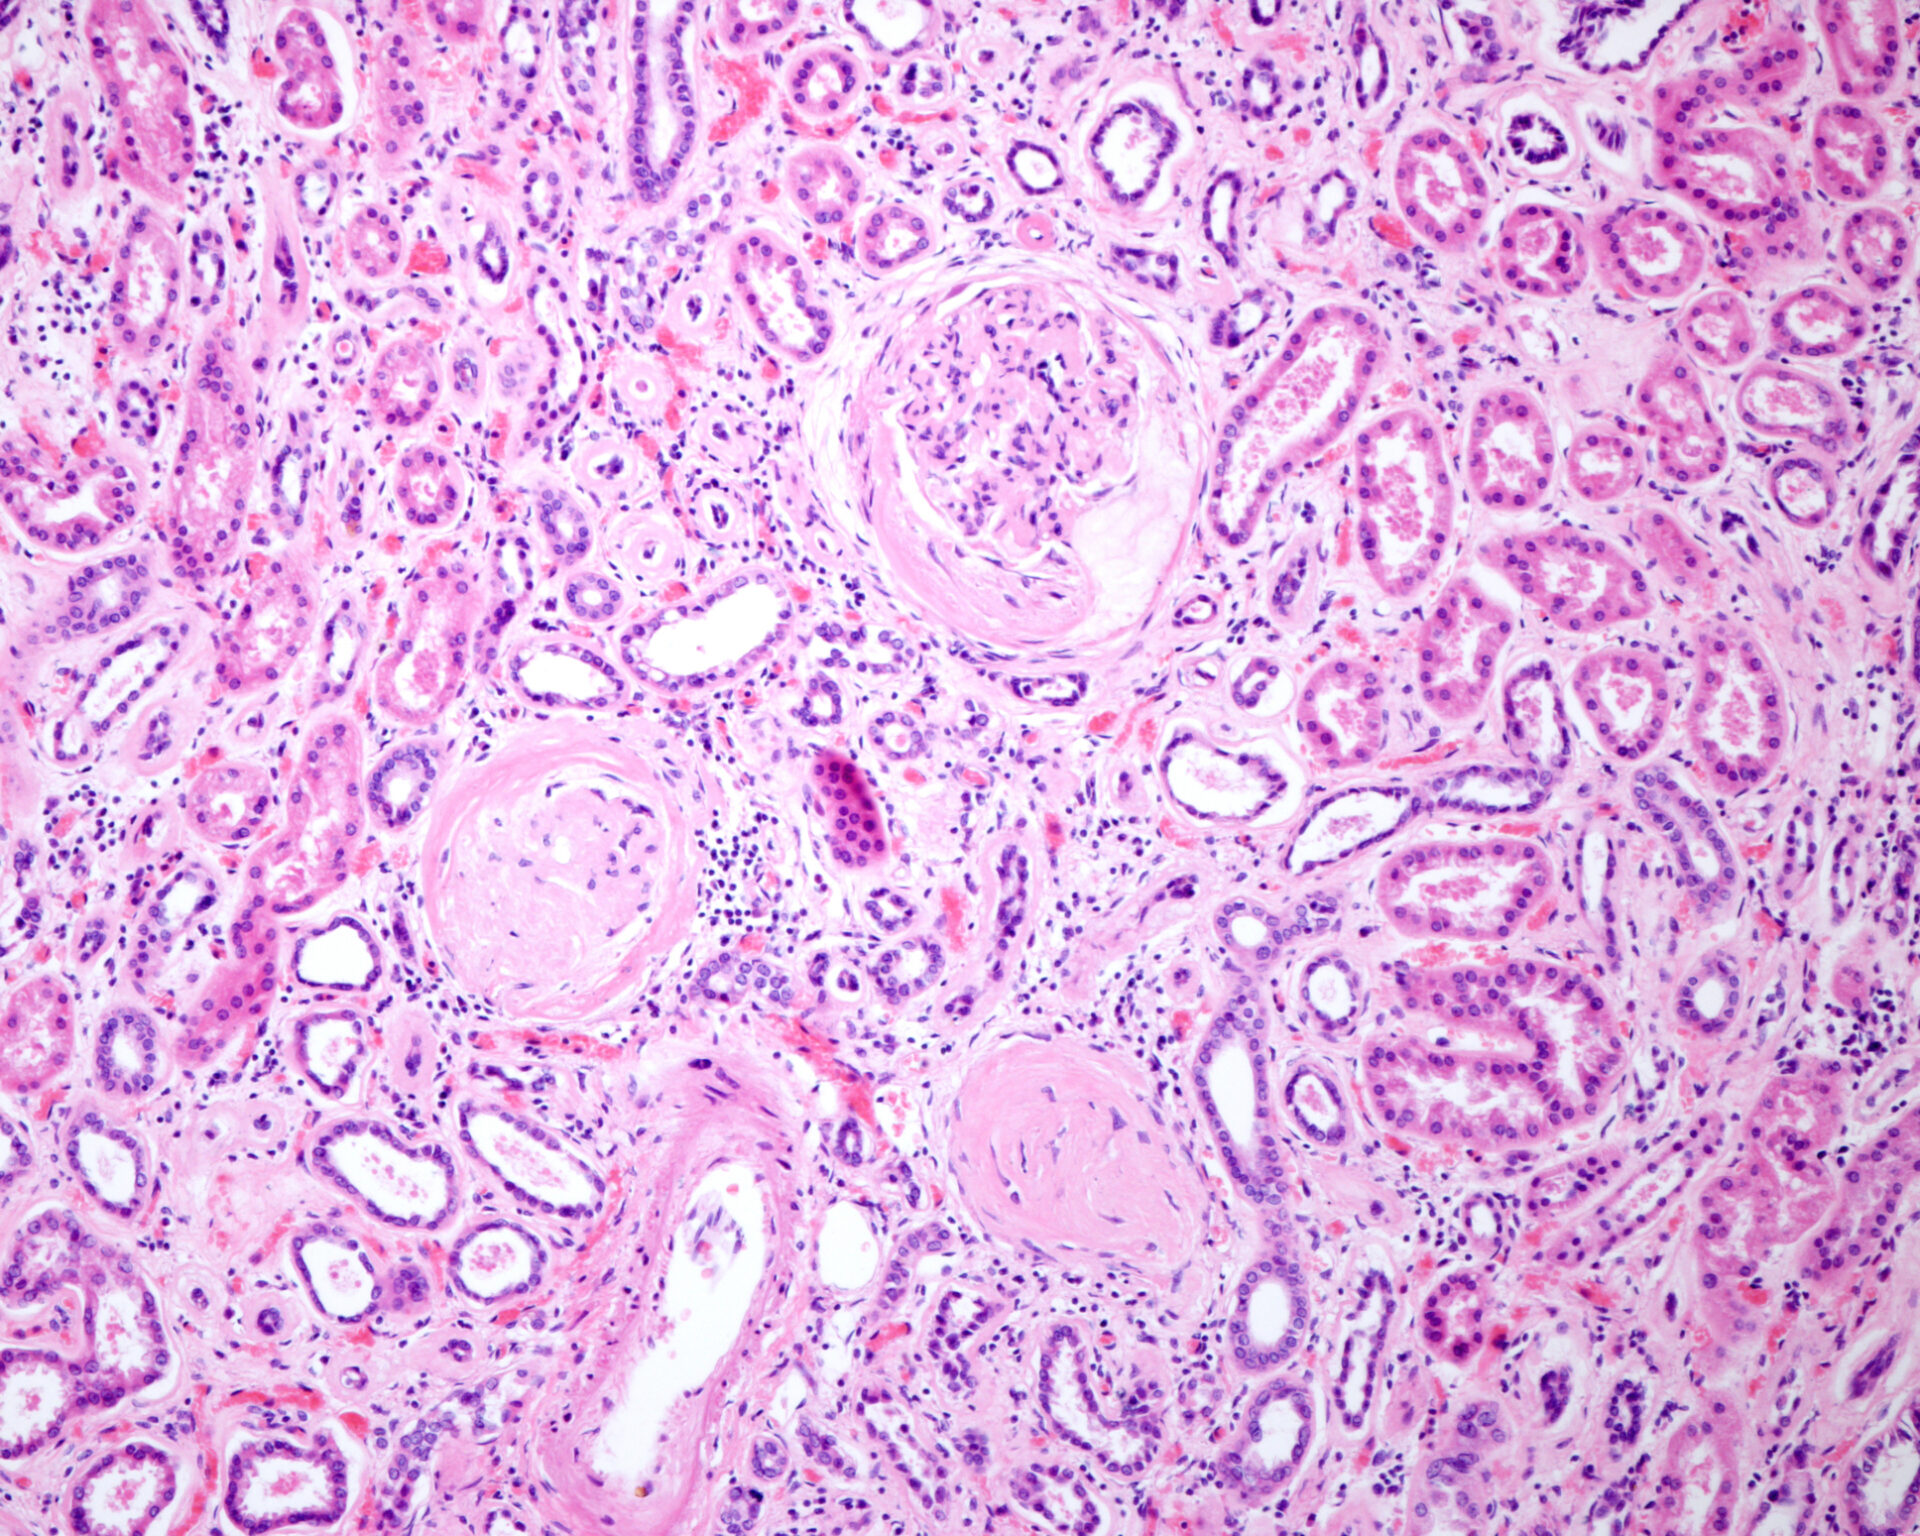

Es wird empfohlen, alle Patienten mit Diabetes routinemässig auf das Vorliegen einer CKD zu screenen. Neben der Messung der glomerulären Filtrations-rate (eGFR) beinhaltet dies auch die Bestimmung der Albumin-Kreatinin-Ratio (UACR). Typ-2-Diabetiker mit CKD profitieren nachweislich von einer Therapie mit einem SGLT-2-Inhibitor und/oder Finerenon, da die Progredienz der Niereninsuffizienz gebremst und das kardiovaskuläre Risiko reduziert wird.